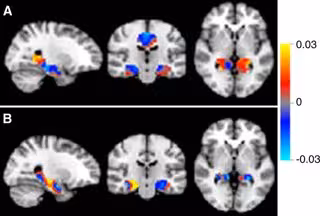

En concreto, esta terapia experimental ha conseguido reducir las placas de proteína tipo beta-amiloide vinculadas al Alzheimer, "lo cual supone un importante paso para el tratamiento de esta enfermedad", según el estudio publicado en Nature.

La investigación señala que esta terapia disminuye la cantidad de proteínas beta-amiloide localizadas en el cerebro de los pacientes con la enfermedad desarrollada de manera leve. Los depósitos de estas proteínas en el cerebro, según los estudios, desempeñan un papel clave en el desarrollo de los síntomas.